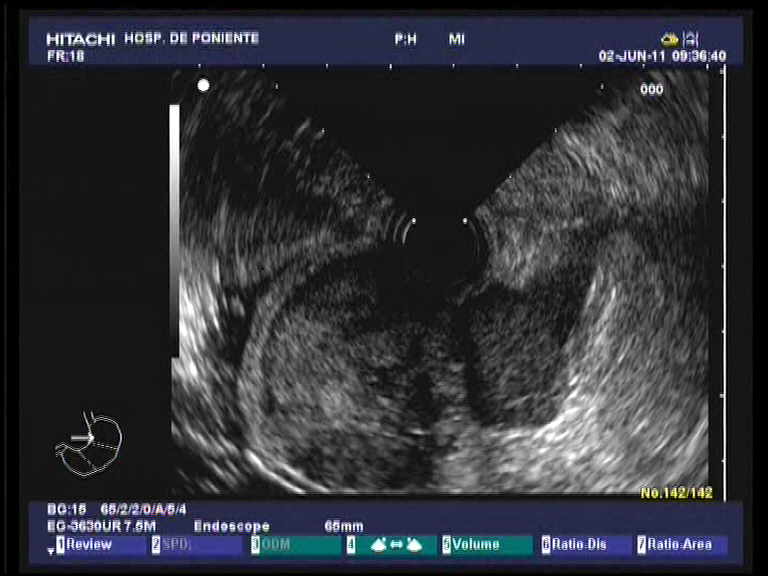

Los tumores GIST (gastrointestinal stromal tumors) son una causa común de lesiones subepieteliales del tracto gastrointestinal. Se consideran lesiones premalignas. De hecho, hasta el 10-30 % de éstas lo son en el momento del diagnóstico. La localización mas común es el estómago. Anteriormente muchas de estas lesiones se catalogaban como leiomiomas gástricos. Su origen se encuentra en las células intersticiales de Cajal y de forma típica, con tinciones de inmunohistoquímica, expresan el marcador CD-117 (también conocido como C-Kit protein; receptor de membrana con actividad para la enzima tirosin-kinasa). Desde el punto de vista endosonográfico se originan en la 4ª capa (muscularis propria), siendo generalmente asintomáticos o manifestándose como HDA (melenas o hematemesis si se ulceran en su vértice, como el caso que se presenta). Suelen ser homogéneos en su ecoestructura. Cuando superan los 3 cm, el borde extraluminal es irregular, aparecen espacios quísticos en su interior o focos hiperecogénicos o bien hay adenopatias perigástricas, existe un mayor riesgo de que sean maligno. El diagnóstico se suele realizar por USE-PAAF, o bien como en este caso, tomando biopsias endoscópicas de la zona ulcerada. La positividad para el C-Kit y el índice mitótico establecen el diagnóstico y su carácter maligno o no. El tratamiento en la mayoría de los casos, cuando son de carácter benigno o localizados, es quirúrgico solamente. Cunado son menores de 2 cm, se confirman que dependen exclusivamente de la 4ª capa y sin afectación local o a distancia, pueden tratarse con la colocación de un lazo (endoloop) y su resección con asa. En casos de malignidad asociado a metástasis ganglionares o a distancia (p.e hepáticas) se basa en la quimioterapia selectiva con inhibidores selectivos de la tirosin-kinasa: imatinib o sunitinib.